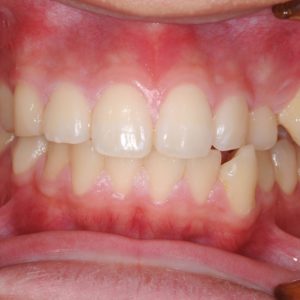

虫歯の治療、矯正の相談をご希望され来院されました。お口の中を診査(レントゲン写真、口腔内写真、視診)させていただいたところ、虫歯については問題なくきれいに歯磨きされているようでした。 正面から見るとジグザグしており、お口 […]

全体的な歯並びの矯正治療を行いました。治療期間は3年間。

ジグザグの歯並びを気にされてご来院されました。. 見た目の問題も大切ですが、それ以上に清掃がしにくいために虫歯・歯周病に非常になりやすく、不正咬合(良くないかみ合わせ)は顎の関節に負担をかけてしまい顎関節症を引き起こす可 […]

歯の大きさに対する顎の大きさのスペース不足により歯が並びきらず、ジグザグの歯並びおよび上の前歯が出っ歯になっていました。 左右4番の歯を抜歯することにより歯を並べるスペースを確保し、歯並びを揃えました。 全体の歯並びが綺 […]